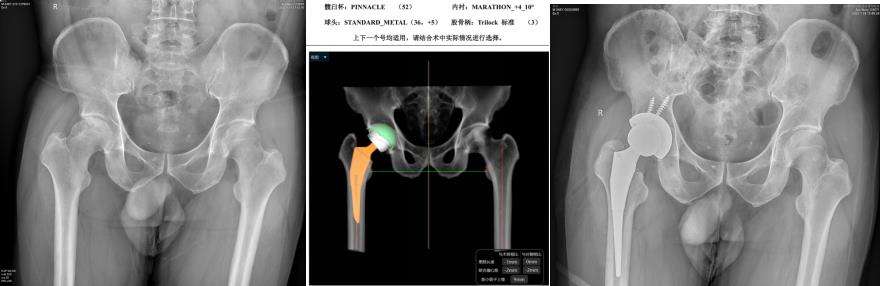

在广西区内率先开展微创DAA全髋关节置换并积累了丰富的病例数和经验,努力实现“术中极限动作不脱位,术后无需限制体位,完全恢复正常活动”。该技术得到同行的高度认可,举办了多期学习班,培养了600多学员,使该技术造福更多的患者。开展关节置换术前AI设计,实现人工关节置换的个体化、精准化重建。

股骨头坏死,行微创DAA全髋关节置换,术前AI设计给精准重建提高保障,术后无需限制体位,术后即可走出手术室,能自由行走、深蹲。